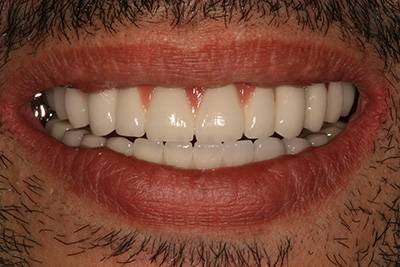

1. eset

A páciens fogágybetegség miatt érkezett hozzánk. A felső fogak menthetetlen állapotban voltak. All on 6 megoldásként a felső fogak eltávolításakor 6 implantátum került beültetésre és a páciens azonnal egy fix ideiglenes hidat kapott. 4 hónapos gyógyulási idő után készült el a felső fémkerámia leplezésű körhíd.